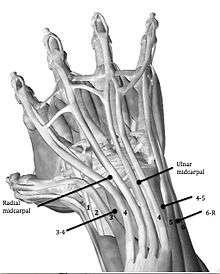

A patient may suffer from various illnesses regarding the wrist. Examples include TFCC lesion, scapholunate and lunotriquetral instability, ganglions, and synovitis. These illnesses concern many different tissues and structures. By using just one portal, one will never be able to visualize all these structures and tissues. For that reason, several portals exist, each having its own function (Table 1).[5] The traditional portals are at the back of the hand (dorsal side), because many neurovascular structures are at risk at the palmar side of the hand.

Dorsal Radial portals The portals lay between the dorsal extensor compartments.[6]

1-2 portal:

- Between the 1st and 2nd extensor compartments

- Located in the Anatomical snuff box

- not often utilized

3-4 portal:

- between the 3rd and 4th extensor compartments

- Located distal to Lister's tubercle

- primary viewing portal

4-5 portal:

- Between the 4th and 5th extensor compartments

- mainly for instrumentation and visualization of TFCC

6R portal:

- at the Radial side of the extensor carpi ulnaris (ECU)

- For TFCC repair

6U portal:

- Located at the Ulnar side of the extensor carpi ulnaris (ECU)

- For TFCC repair

Volar radiocarpal(VR) portal

- This portal is used for evaluation the dorsal radiocarpal ligament(DRCL) and the scapolunate interosseus ligament (SLIL)

Midcarpal portals:

Midcarpal Radial portal (MCR)

- Allows visualization of the scapholunate(SL), scaphocapitate(SC) and scaphotrapezoid(ST) joints.

Midcarpal Ulnar portal (MCU)

- Allows visualization of the lunocapitate(LC), lunotriquetral(LT) and triquetrohamate (TH)joints.

Dorsal Distal Radioulnar joint portal (DDRUJ)

Volar Distal Radioulnar joint portal (VDRUJ)

- Used for assessing the TFCC attachment